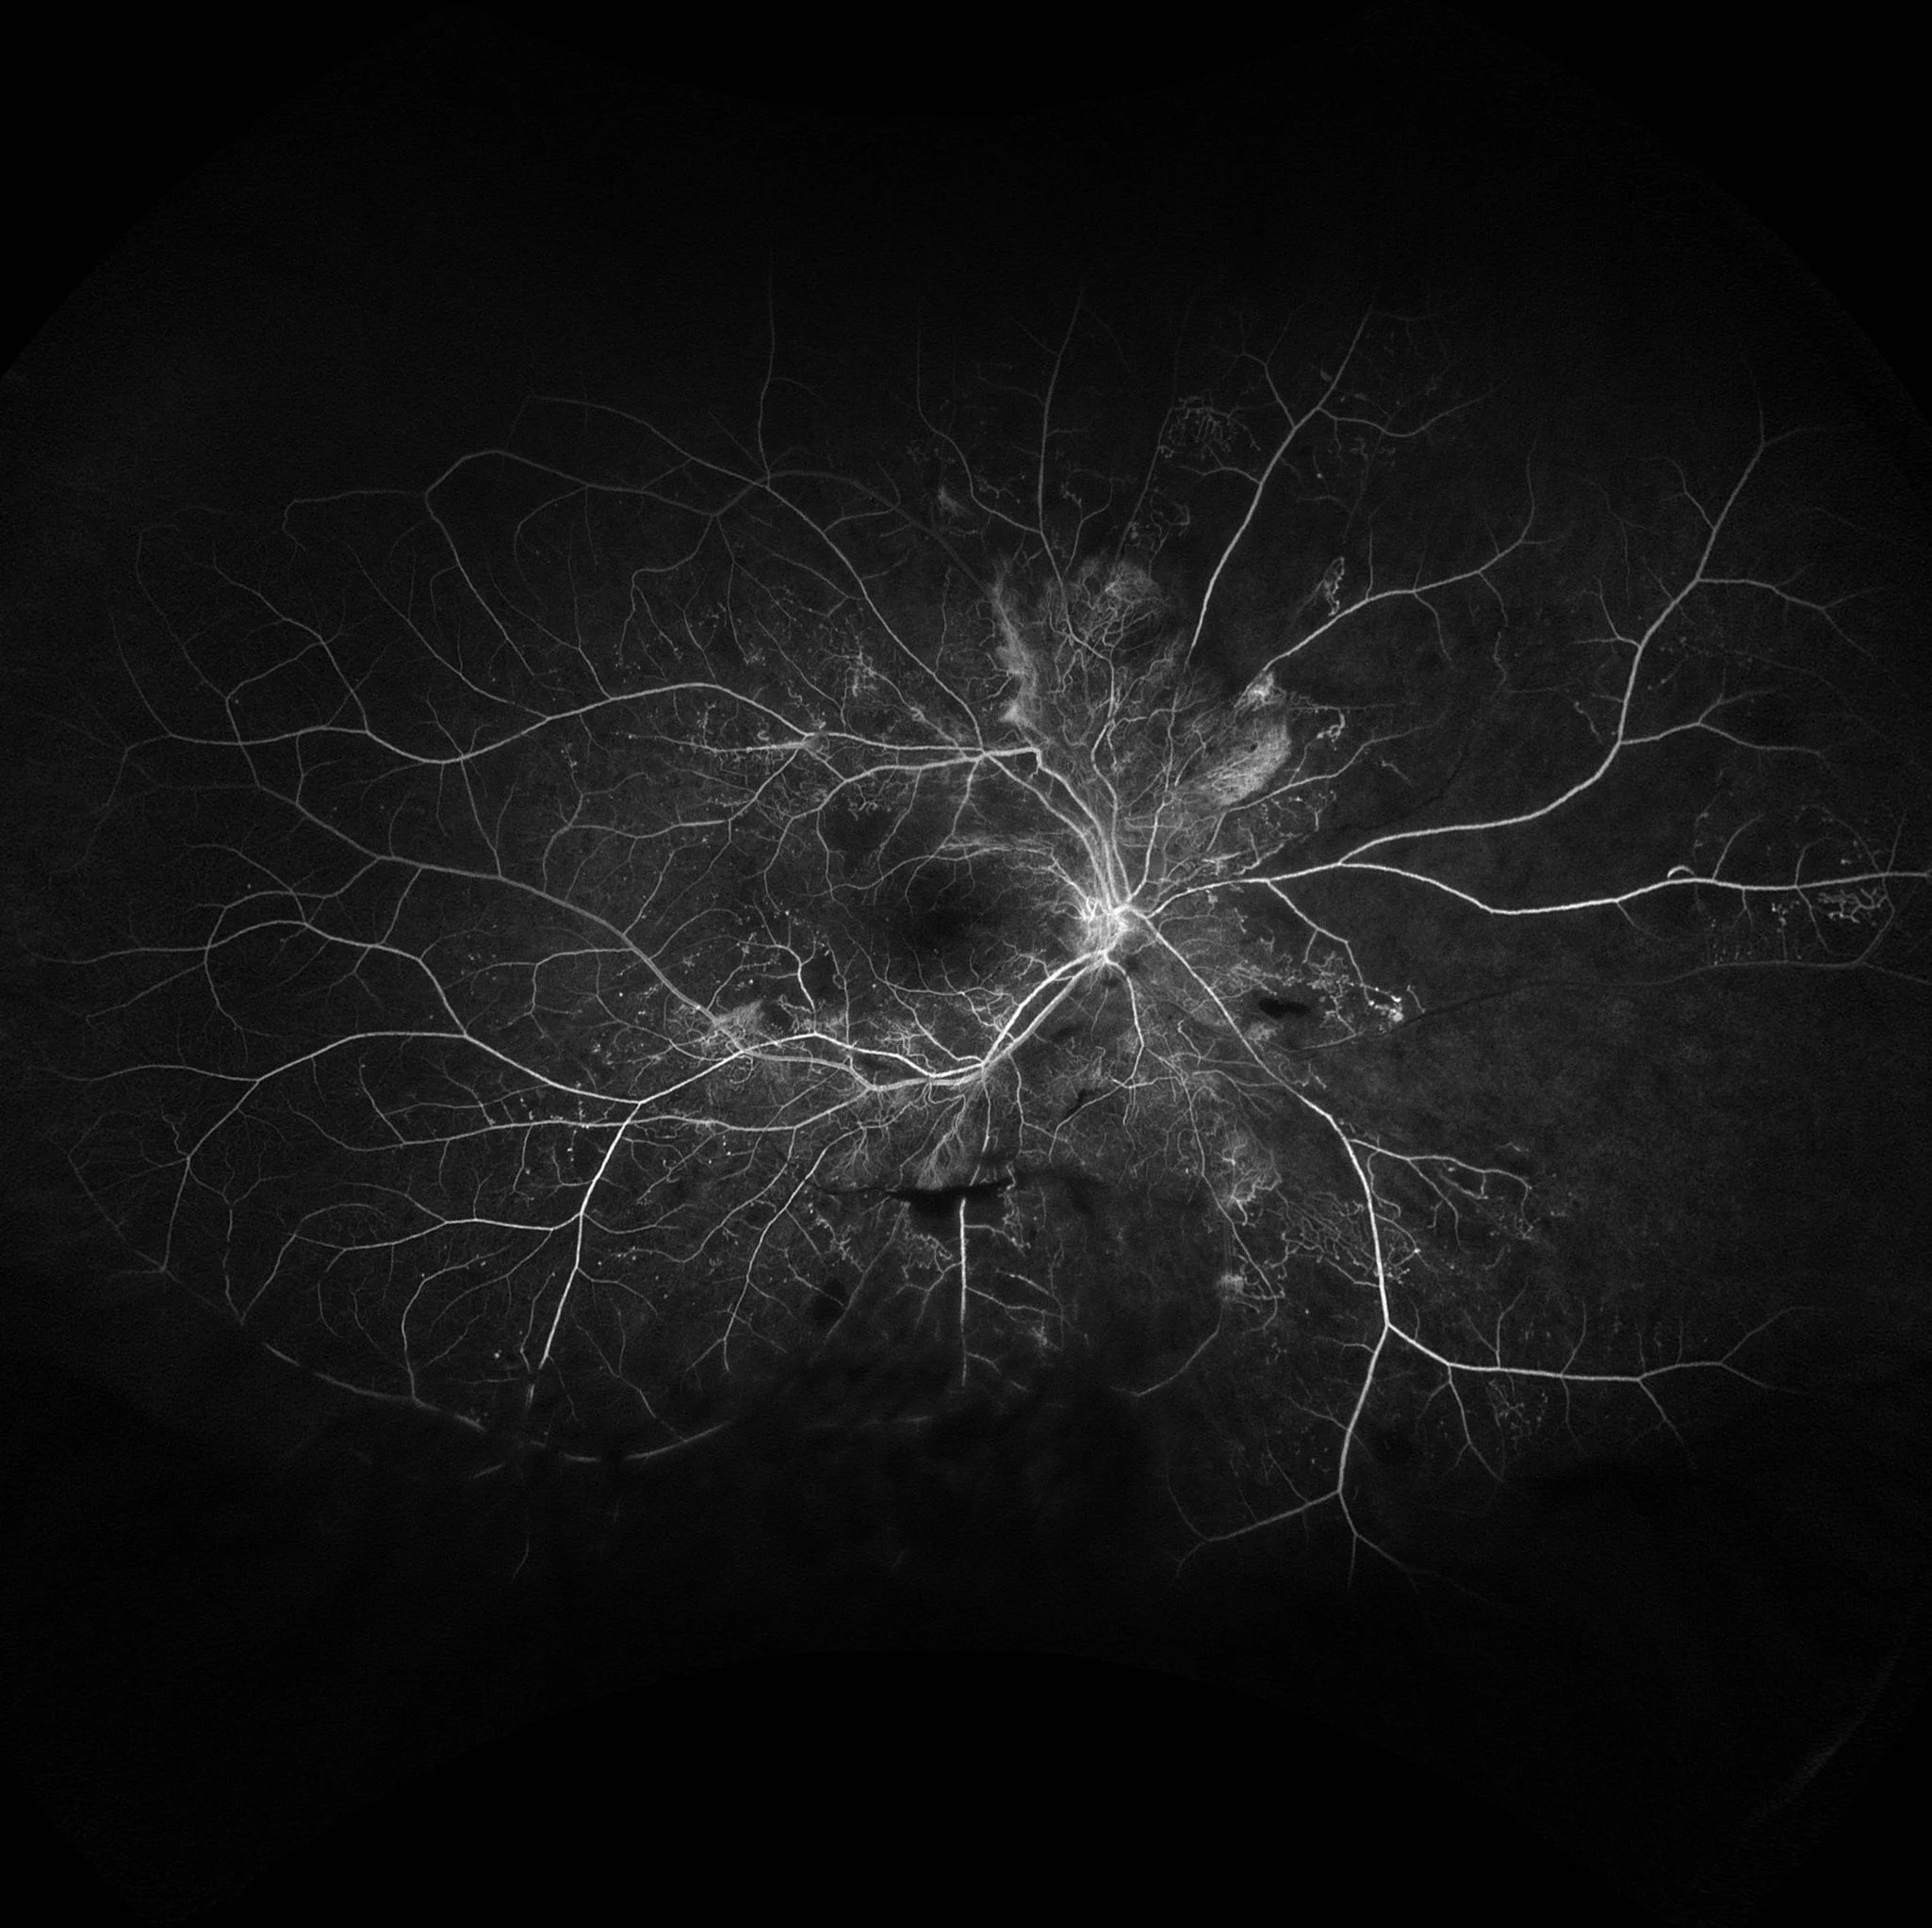

Proliferative Diabetic Retinopathy

This is a severe case of proliferative diabetic retinopathy, with neovascularization at the disc and peri-papillary areas. Abnormal vessel formation, that are friable and leaky, lead to hyperfluorescence with indistinct borders that widens and intensifies as the angiogram progresses.

Notice the extensive occlusive disease and non-perfusion due to capillary drop out in the periphery.